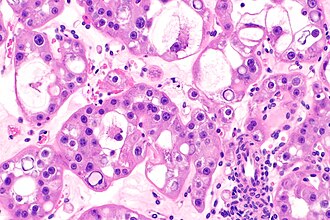

| Caption = Hybrid oncocytic/chromophobe tumour of the kidney. [[H&E stain]]. | | Caption = Hybrid oncocytic/chromophobe tumour of the kidney. [[H&E stain]]. | ||

Hybrid oncocytic/chromophobe tumour of the kidney. H&E stain. | |

| LM | features of renal oncocytoma and chromophobe renal cell carcinoma - varies by subtype |

| Subtypes | as per Hes et al.: (1) collision tumour-type, (2) renal oncocytoma with scattered chromophobe cells-type, (3) large eosinophilic cells with intracytoplasmic vacuoles-type |

Renal hybrid oncocytic/chromophobe tumour, also hybrid oncocytic/chromophobe tumour (abbreviated HOCT) and hybrid tumour, is a rare kidney tumour with features of chromophobe renal cell carcinoma and renal oncocytoma.[1]

Three morphologic patterns as per Hes et al.:[1]

- Renal oncocytoma and chromophobe renal cell carcinoma collision tumour.

- Different fields viewed in isolation would be compatible with the different diagnoses. Tumour component do not intermingle.

- Renal oncocytoma with scattered chromophobe cells.

- Large eosinophilic cell with intracytoplasmic vacuoles - this is the evolving entity eosinophilic vacuolated tumour.

- Prominent nucleoli (ISUP nucleolar grade 3).

- Perinuclear halos (occasional).

- Nested architecture.